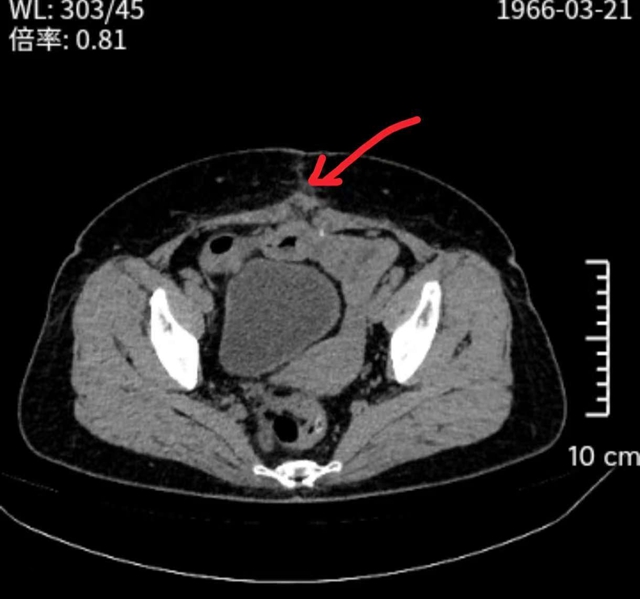

修补后

凭借精湛的微创技术和默契的团队配合,手术团队小心翼翼地分离粘连、复位疝出组织、精准植入补片、妥善固定。历经3个小时的奋战,手术圆满完成。术后,王阿姨恢复良好,下腹部的“大包”彻底消失,腹痛、腹胀症状也明显缓解,困扰多年的顽疾终于得到了解决。